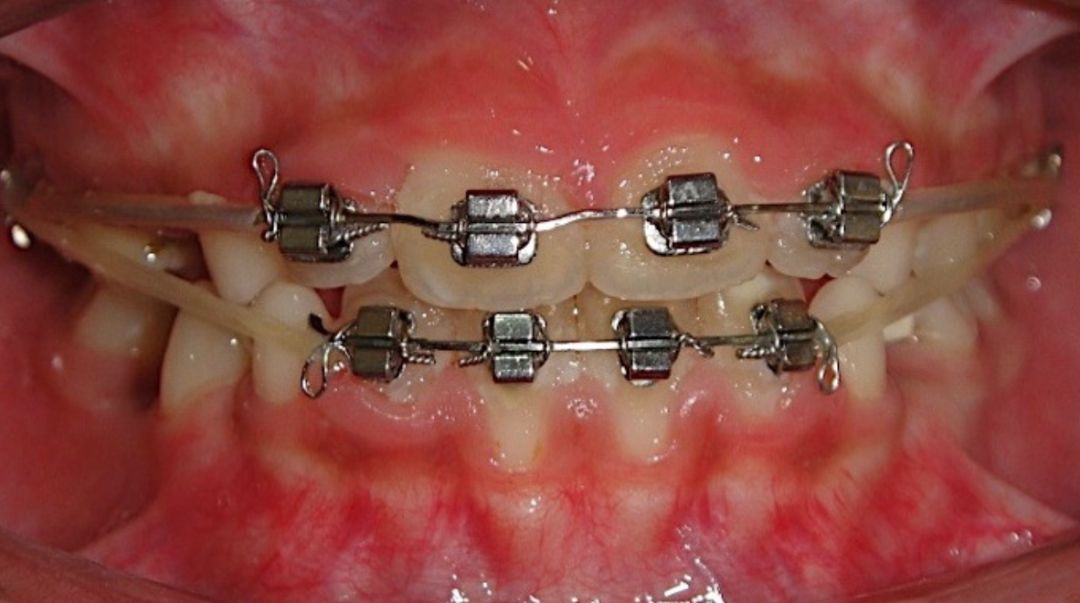

2.简单的固定矫正

由铁丝与托槽组成的矫治系统,也就是大家最熟知的钢丝牙套,也可以用于儿童牙齿早期的矫正治疗。